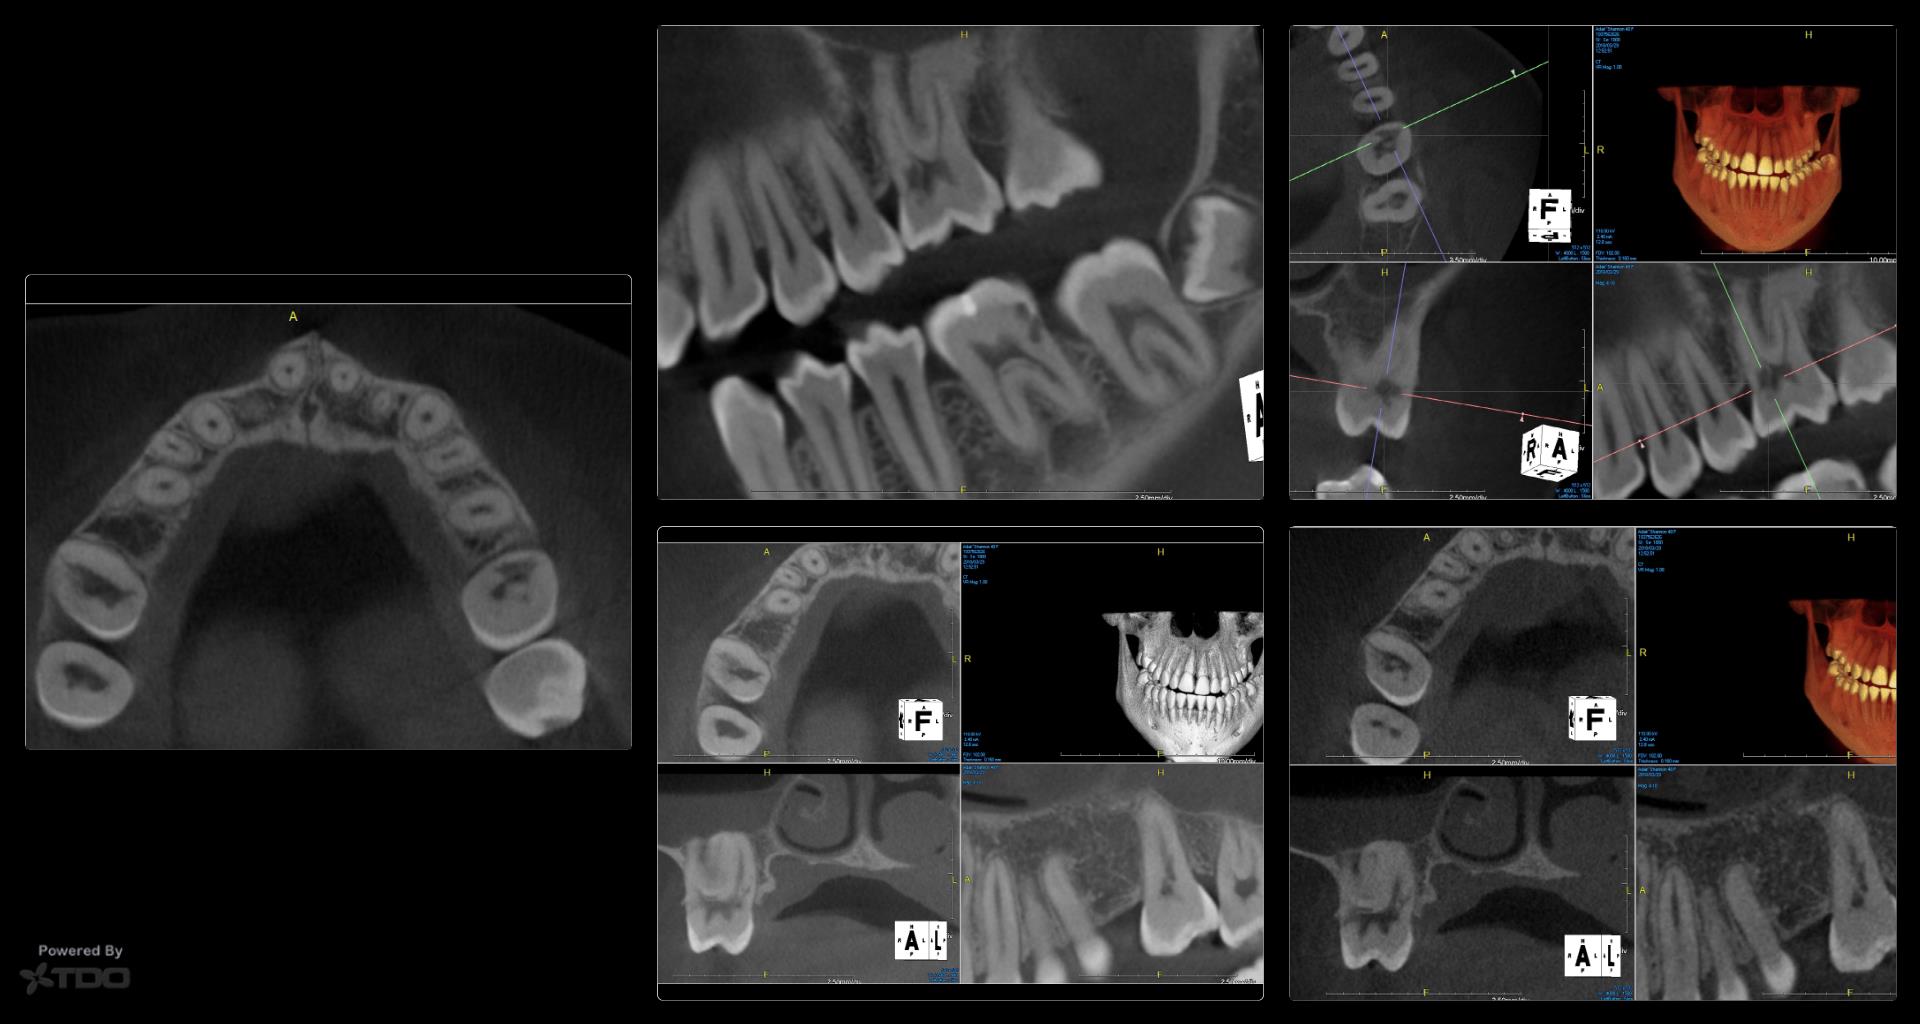

The answer I wanted, given the history of ortho, is that you want to scan other areas of the mouth to see if other areas are involved as well.

For example in this same case…….

Given what we know, and being mindful of all we don’t know, my decision of no treatment is dominated by the consideration of a Class III ECIR with very evident furcal evidence of resorption (where there is no access to the vascular channels) and hence the “smartest bet” is avoid the impulse to be a hero.